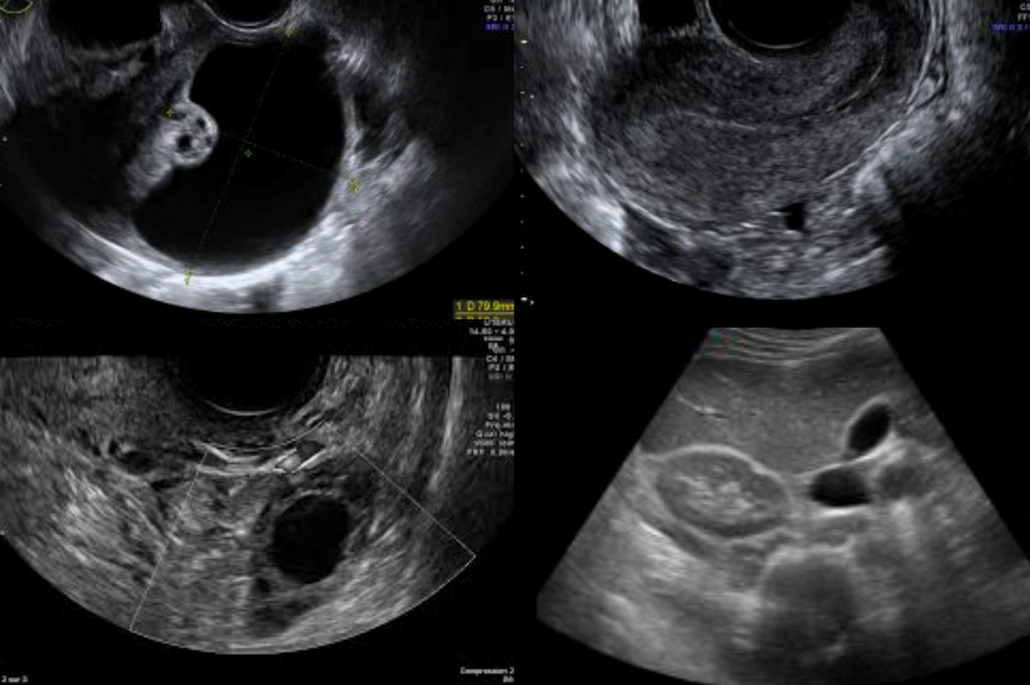

Trois mois plus tard, Mlle C. revient pour le contrôle clinico-échographique. Elle est asymptomatique, cycles réguliers, aucune douleur. Voici son échographie.

Figure 4 (Rodolphe Matias de Sousa, La Revue du Praticien)

Question 3 - Quel(s) critère(s) suspect(s) de malignité objectivez-vous sur cette image d’échographie endovaginale ?

Les cloisons sont épaissies et irrégulières.

L’aspect anéchogène avec un renforcement hyperéchogène postérieur (les ultrasons n’ont pas été atténués par le liquide présent dans le kyste contrairement à ceux ayant traversé le reste des tissus) est en faveur de la présence de liquide à l’intérieur du kyste. Les kystes fonctionnels bénins sont justement liquidiens purs.

Les principaux critères échographiques en faveur de la malignité d’un kyste ovarien sont la présence de composantes solides (végétations, paroi/cloisons épaisses), la vascularisation Doppler suspecte, l’ascite et certains critères de taille et de bilatéralité.

Figure 5 (Rodolphe Matias de Sousa, La Revue du Praticien)